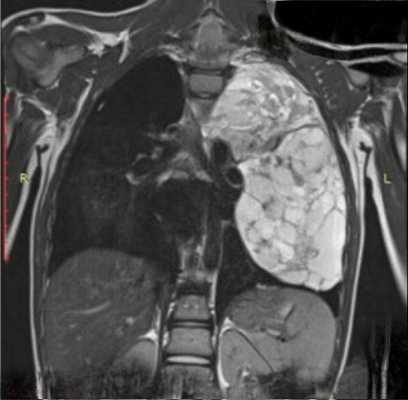

В тех случаях, когда эти опухоли (что, к счастью, бывает редко) озлокачествляются и приобретают крупные размеры, тогда судить о природе, источнике чрезвычайно сложно. Это злокачественная нейрогенная опухоль, которая привела к оттеснению средостения в противоположную сторону - в сторону правого легкого с накоплением жидкости в правой половине плевральной полости.

Огромных размеров патологическое образование, оттесняющее аорту впереди в сторону сердца, занимающее практически всю левую половину грудной полости, оттесняющее селезенку, почку и диафрагму вниз. Это злокачественная нейрогенная опухоль. Но сказать о том, что эта опухоль исходит из нервных образований, при томографическом исследовании очень сложно и не всегда возможно.